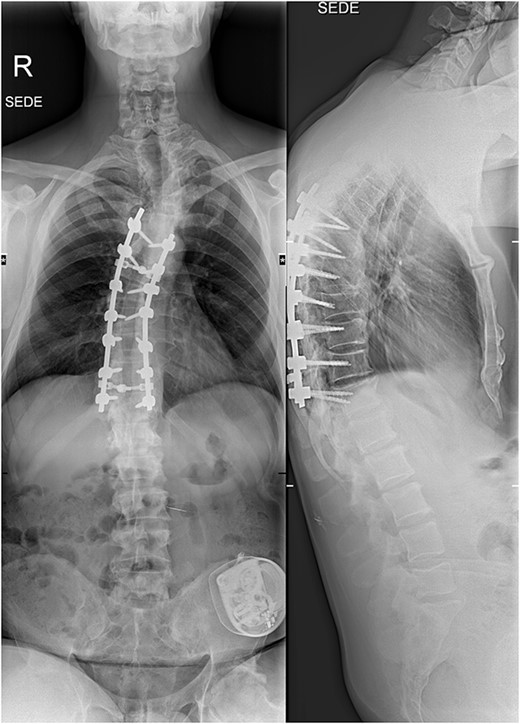

The imaging studies revealed thoracic kyphoscoliosis (with a kyphotic curve of 50°, left upper-thoracic curve of 40° and right lower-thoracic curve of 25°) and significant stenosis of the thoracic part of the spinal canal (particularly at levels Th6, Th9 and Th11) due to severely ankylosed ligamentum flavum (OLF) and the concomitant degeneration of the facets (Figs 1 and 2). Imaging indicated thoracic myelopathy (Fig. 3). We performed emergent posterior wide laminectomy using an ultrasound bone scalpel, and a partial correction of the deformity by instrumented spinal fusion (Th6-Th12). The surgery was performed by the senior author (N.H.).

The initial X-ray images of the thoracic spine at the time of admission to our institution. Anteroposterior view (left) and lateral view (right).